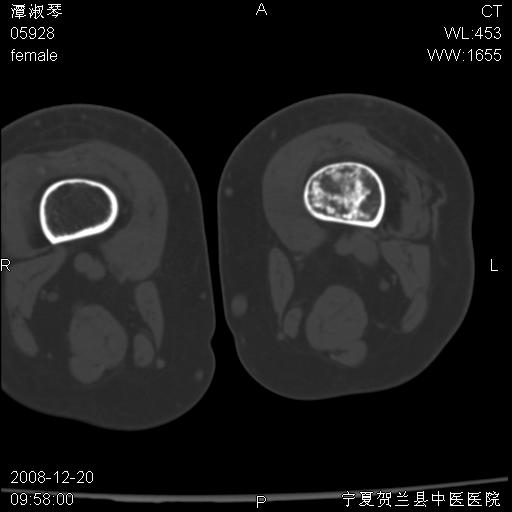

标题: CT17526:请各位看看是啥?

内生软骨瘤?骨梗死?

考虑内生软骨瘤可能性大

考虑-----骨梗死+退变

支持骨梗死,退行性骨关节病,膝关节积液.

考虑骨梗死可能性大

支持骨纤或内生软骨瘤或骨梗死,退行性骨关节病,膝关节积液.

骨梗死可能性大

左股骨下段骨梗死。双膝退变。

支持:内生软骨瘤或骨梗死!另:退行性骨关节病,膝关节积液。

左胫骨下端松质骨及髓腔内可见点片状高密度灶,骨皮质无明显膨胀及变薄。病变范围较长。支持骨梗死,退行性骨关节病,膝关节积液